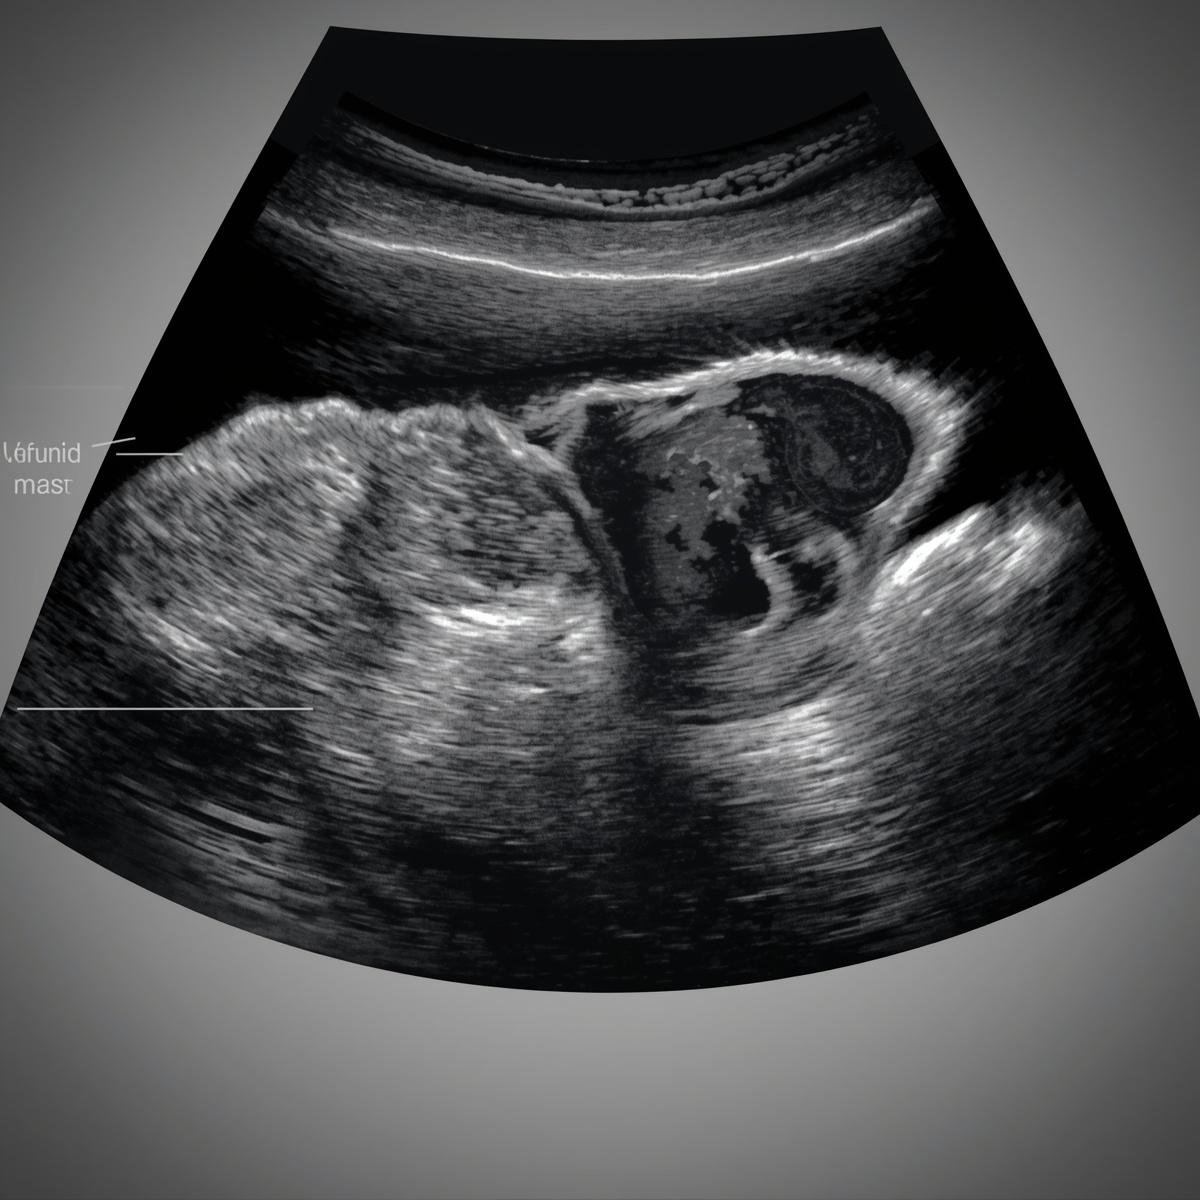

Gynae surgery involves surgical procedures used to treat conditions affecting the female reproductive system, such as the uterus, ovaries, and fallopian tubes. It is performed to manage problems like fibroids, ovarian cysts, and other gynecological conditions. Modern surgical techniques help ensure safe treatment and faster recovery for patients.

Ovarian Cyst Removal

Surgery performed to remove cysts from the ovaries while maintaining healthy ovarian tissue.

Ectopic Pregnancy Surgery

Emergency surgery performed when a pregnancy develops outside the uterus.